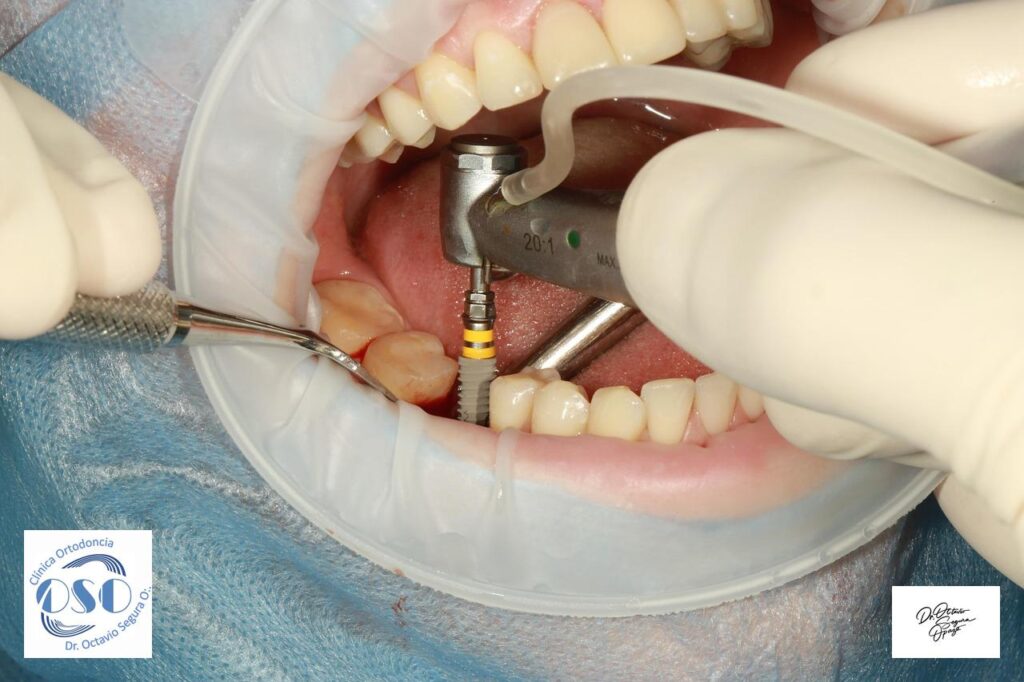

Clínica Ortodoncia Doctor Octavio Segura O.: Información Relevante Ortodoncia en Castro: Todo lo que debes saber para mejorar tu sonrisa ¿Buscas un tratamiento de ortodoncia en Castro que sea seguro, profesional y con resultados garantizados? En este artículo te contamos todo lo que necesitas saber ... Leer más → Implantes cortos en sector posterior de maxilar inferior Leer documento sobre implantes cortos (Short) ¿Es necesaria la exodoncia preventiva de treceros Molares? ¿Son los implantes para toda la vida? Enfermedad Periodontal y Vitamina D